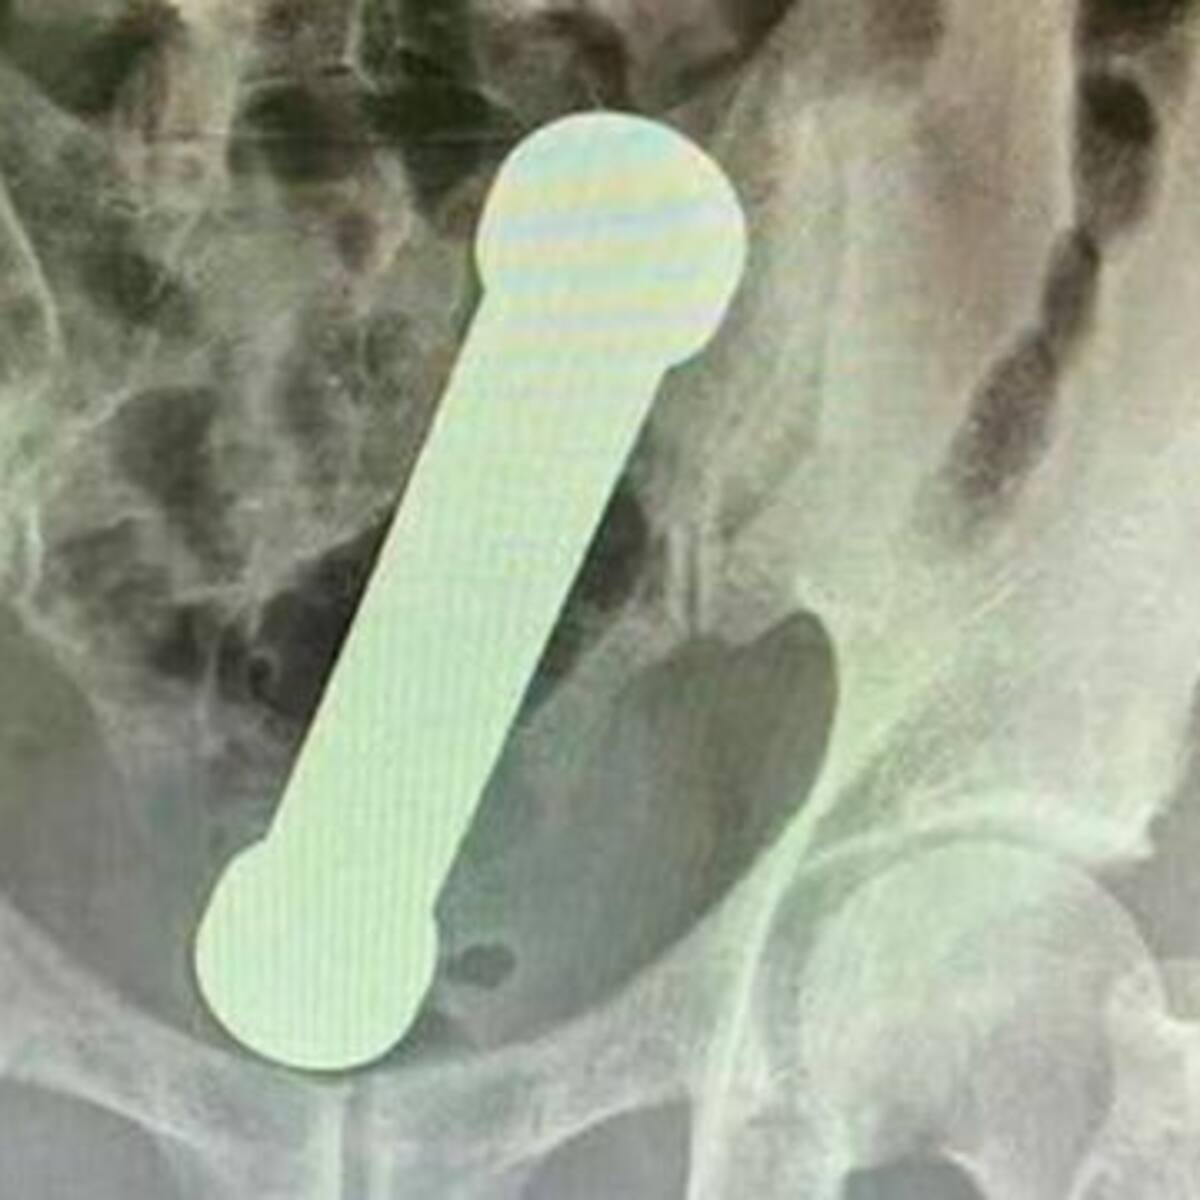

Un hombre dejó sorprendidos a los médicos luego de que le encontraran el objeto incrustado en su intestino.

LOS40 Colombia

16/04/2022